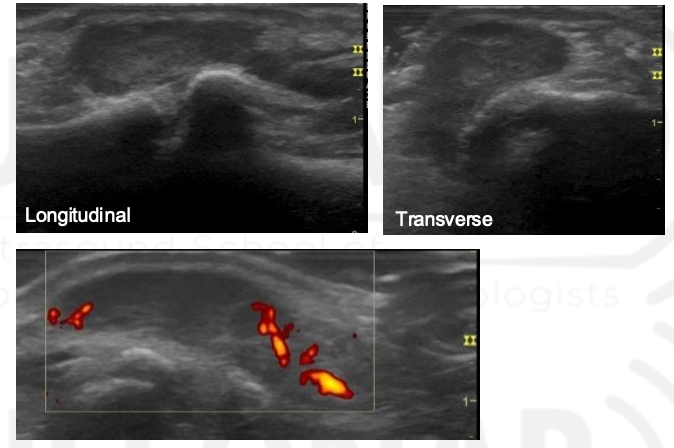

Grade The Synovial Hypertrophy

Grade this

B: grade 1 (up to 3 single signals — 1 confluent + 2 single — 2 confluent)

Minimal synovial hypertrophy up to the imaginary horizontal line connecting 2 joints; Power Doppler up to 3 single signals — 1 confluent + 2 single — 2 confluent

Grade 1: minimal

Moderate synovial hypertrophy protruding over the joint line along with concave surface; Larger than grade 1 but <50% of synovial hypertrophy covered by signals

Grade 2: moderate

Severe synovial hypertrophy producing beyond the joint line with convex surface; more than 50% of SH area covered by signals

Grade 3: Severe

Grade this doppler

Grade 2: Larger than grade 1 + <50% of SH area

Grade 3: >50% of the synovial hypertrophy is covered by signals